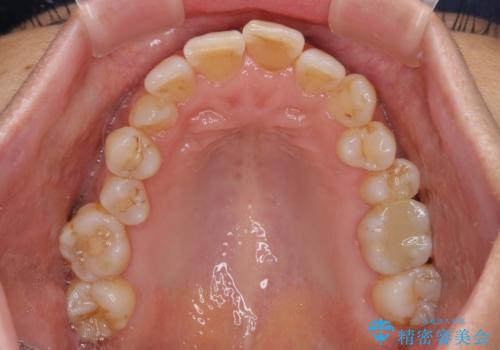

- 骨格的な咬み合わせのズレ、前歯のデコボコとクロスバイトを気にして来院された患者様です。

奥歯の噛みにくさが顕著なためマウスピースではなく、ワイヤー装置による矯正治療を行うこととしました。

下顎の正中を歯1本分ずらした位置とすることで、外見上の骨格的なずれをカバーするように計画しました。

クロスバイトを改善したことで、前歯の負担が軽減し、安定して噛めるようになりました。